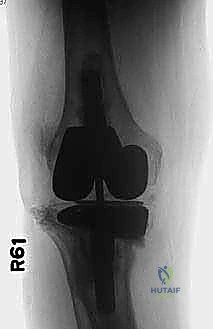

يعتمد الدكتور هطيف على أحدث تقنيات التصوير الطبي، بما في ذلك الأشعة السينية الرقمية (Digital X-rays) في وضعيات الوقوف، والتصوير المقطعي المحوسب (CT Scan) ثلاثي الأبعاد لتقييم حجم العظم المتبقي بدقة متناهية. كما يتم إجراء فحوصات دم شاملة وسحب سائل من الركبة (Aspiration) لاستبعاد وجود أي عدوى بكتيرية خفية.

خطوتنا الجراحية الأولى هي التصنيف الدقيق لمدى فقدان العظم في الجزء العلوي من عظم الساق (الظنبوب). هذا التصنيف يوجهنا كبوصلة في اختيار الغرسة المناسبة والاستراتيجية الجراحية. نستخدم بشكل أساسي نظام تصنيف عيوب العظم لمعهد أندرسون لجراحة العظام (AORI bone defect classification system). يصنف هذا النظام العيوب بناءً على حالة العظم الميتافيزي في الصور الشعاعية:

- عيوب النوع الثاني (Type II Defects): هنا، نلاحظ تلفاً واضحاً في العظم الميتافيزي، غالباً مع هبوط في مكونات المفصل أو تغيير في خط المفصل بسبب فقدان بؤري للعظم. يمكن أن يشمل هذا الفقدان الهضبة الظنبوبية الجانبية أو الإنسية (الأكثر شيوعاً)، أو حتى الجزء العلوي بأكمله. الأهم من ذلك، في عيوب النوع الثاني، تكون الأربطة الجانبية محفوظة عادةً. يتطلب إعادة البناء هنا استخدام الدعامات المعدنية (الكتل أو الأوتاد) لإعادة إنشاء خط المفصل المستوي، وغالباً ما تُستخدم سيقان معدنية قصيرة.

- عيوب النوع الثالث (Type III Defects): هذه هي الفئة الأكثر شدة وتدميراً. تتميز بنقص هائل في العظم الميتافيزي العلوي يشمل جزءاً كبيراً من الجزء العلوي من عظم الساق. قد يشمل التدمير الحدبة الظنبوبية، وقد تكون الأربطة الجانبية غير كفؤة وظيفياً بسبب فقدان مرتكزاتها العظمية. تتطلب هذه العيوب المعقدة استخدام دعامات معدنية متقدمة جداً (مثل المخاريط والأكمام المعدنية المسامية - Cones and Sleeves) مع غرسات ذات سيقان طويلة تتجاوز منطقة الخلل للوصول إلى العظم السليم في منتصف الساق.

3. تنظيف العظم وتقييم العيب (Debridement and Assessment)

بعد إزالة المفصل، يتم تنظيف العظم بالكامل من أي أنسجة ملتهبة أو أسمنت متبقي. هنا، تتجلى الرؤية الحقيقية لحجم العيب العظمي (AORI Type II أو III). يتم قياس الفجوات العظمية بدقة باستخدام قوالب تجريبية.